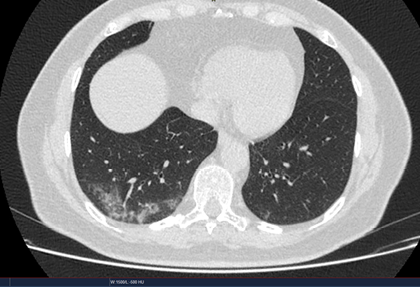

Routine clinical laboratory assays were performed in the hospital’s clinical laboratories. Clinical and laboratory information was extracted from the patients’ medical records. C reactive protein (CRP) in plasma was measured by immunoturbidimetry (Beckman Coulter, Krefeld, Germany). Interleukin-6 (IL-6) levels in plasma were measured by electrochemiluminescence (Siemens Medical Solutions Diagnostics, Siemens Healthcare, Erlangen, Germany). CT scans were read by experienced radiologists who scored results by severity using the criteria shown in Figure 1.

Figure 1. Clinical assessment of pneumonia severity based on computed tomography (CT) scores.

Scoring method: Mild (CT-1)—no more than three ground-glass opacities of <3 cm maximum diameter. Moderate (CT-2)—more than three ground-glass opacities; less than 50% involvement by visual assessment. Medium-heavy (CT-3)—ground-glass opacities and pulmonary consolidation; 50-70% involvement by visual assessment. Severe (CT-4)—diffuse ground-glass opacities with or without consolidation; more than 75% involvement by visual assessment.